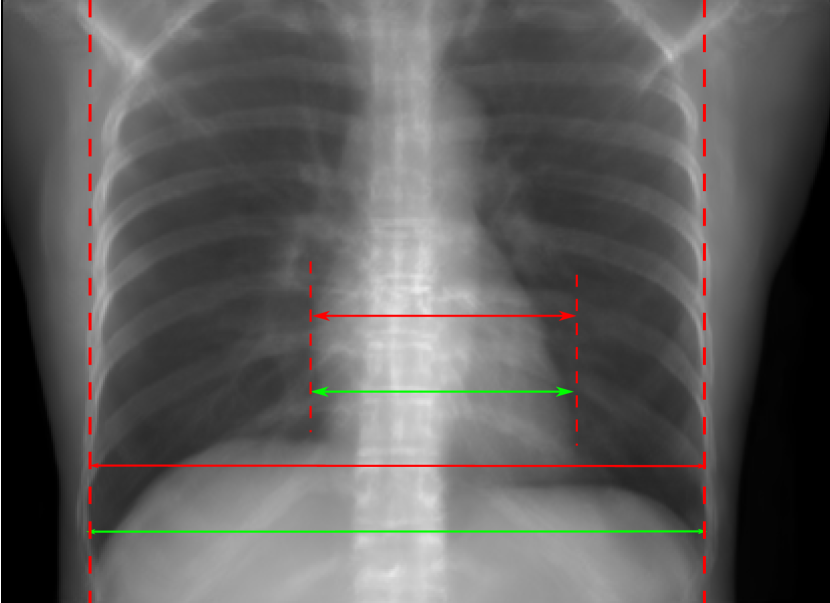

Figure 10: Perspective deformation learning in one exemplary patient case for chest X-ray imaging. The maximal horizontal cardiac diameter and the maximal horizontal thoracic diameter in (b) and (d)-(f) are indicated by the horizontal red lines, while those in the reference image (a) are green lines. The cardiothoracic ratio, RMSE, and SSIM for each image is displayed in its corresponding subcaption.

The results of one patient in chest X-ray imaging are displayed in Fig. 10, where the cardiothoracic ratio is assessed as an exemplary clinical application [32]. In the reference image (Fig. 10(a)), the maximal horizontal cardiac diameter (MHCD) and the maximal horizontal thoracic diameter (MHTD) are indicated by two green horizontal lines. Its cardiothoracic ratio is 0.4237. In the 0superscript00^{\circ} perspective projection image (Fig. 10(b)), all the anatomical structures can be visualized with fine resolution. However, due to perspective deformation, anatomical structures, e.g. the ribs and the spine, are deformed. The deformations are visualized better in the difference image Fig. 10(c). Compared with the ribs and the spine, the heart has less deformation as its location is closer to the isocenter. In Fig. 10(b), the MHCD and the MHTD are indicated by two red horizontal lines, while the green lines are those of the reference image. While the MHCD has changed little from 10.47 cm to 10.16 cm, the MHTD has changed considerably from 24.71 cm to 25.40 cm. As a consequence, the cardiothoracic ratio becomes 0.4002, which is below the normal range of 0.42 - 0.50 [32]. The result of learning perspective deformation from 0superscript00^{\circ} single view is displayed in Fig. 10(d), where the MHCD and the MHTD are 10.63 cm and 24.71 cm, respectively. The MHTD of Fig. 10(d) is the same as that of the reference image. This is also reflected by the difference image Fig. 10(g), where the lower ribs have small errors. However, the upper ribs as well as the spine still have considerable errors. The results of perspective deformation learning from 0&180superscript0superscript1800^{\circ}\&180^{\circ} views in Cartesian and polar coordinates are displayed in Fig. 10(e) and Fig. 10(f), respectively. The measured MHCDs and MHTDs in these two images are very close to the reference ones. Hence, their cardiothoracic ratios, 0.4214 and 0.4240 respectively, are close to the reference ratio as well. In the difference images (Fig. 10(h) and Fig. 10(i)), the errors of ribs and spine decrease as their boundaries are no longer apparently visible. Nevertheless, Fig. 10(i) has less error than Fig. 10(h), achieving the smallest RMSE value of 3.83. The quantitative evaluation of all the 162 testing datasets is displayed in Tab. II, where learning perspective deformation from two complementary views in polar coordinates achieves the least RMSE 4.98 and highest SSIM 0.9517, demonstrating the superiority of learning perspective deformation from two complementary views in polar coordinates.

The TransU-Net results are displayed in Figs. 10(j)-(l). Compared with their corresponding Pix2pixGAN results, the TransU-Net prediction images are more blurry, although the same perceptual loss is used. The error images in Figs. 10(m)-(o) indicate that TransU-Net reduces perspective deformation better with complementary views than a single view. The quantitative evaluation in Tab. II shows that TransU-Net cannot effectively reduce perspective deformation with a single view. With complementary views in both Cartesian and polar coordinate systems, TransU-Net achieves comparable performance, which is still considerably worse than that of Pix2pixGAN. The inferior performance of TransU-Net to Pix2pixGAN on the chest data is potentially caused by the repetitive nature of the segmental rib anatomy, which leads TransU-Net to be ineffective in extracting position-dependent features.